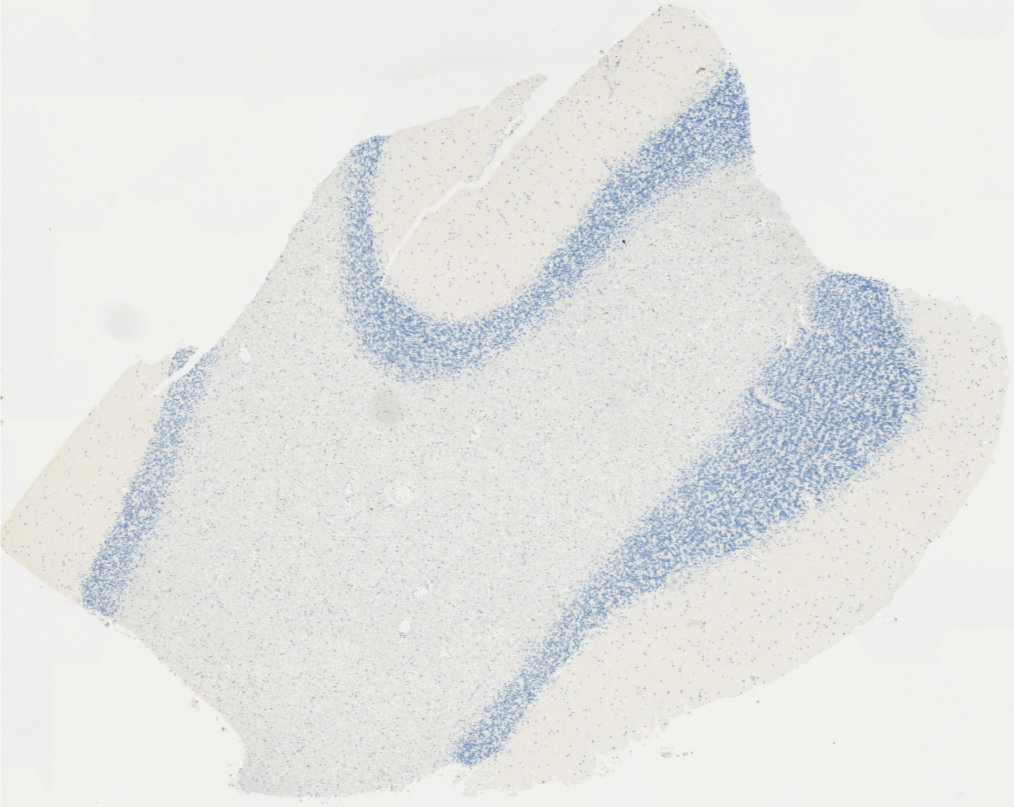

Los escáneres o digitalizadores de láminas son microscopios automatizados capaces de capturar imágenes digitales idealmente en alta resolución a partir de láminas histológicas físicas. Existen distintos modelos según el volumen y la aplicación clínica, pero para diagnóstico deben cumplir estándares estrictos de calidad y precisión.

Digitalizamos tus láminas y entregamos archivos listos para diagnóstico, revisión o docencia, con imágenes de alta resolución que cumplen estándares internacionales y que pueden ser fácilmente integradas por sistemas LIS.

Material digitalizado para docencia, análisis y bibliotecas digitales histológicas.